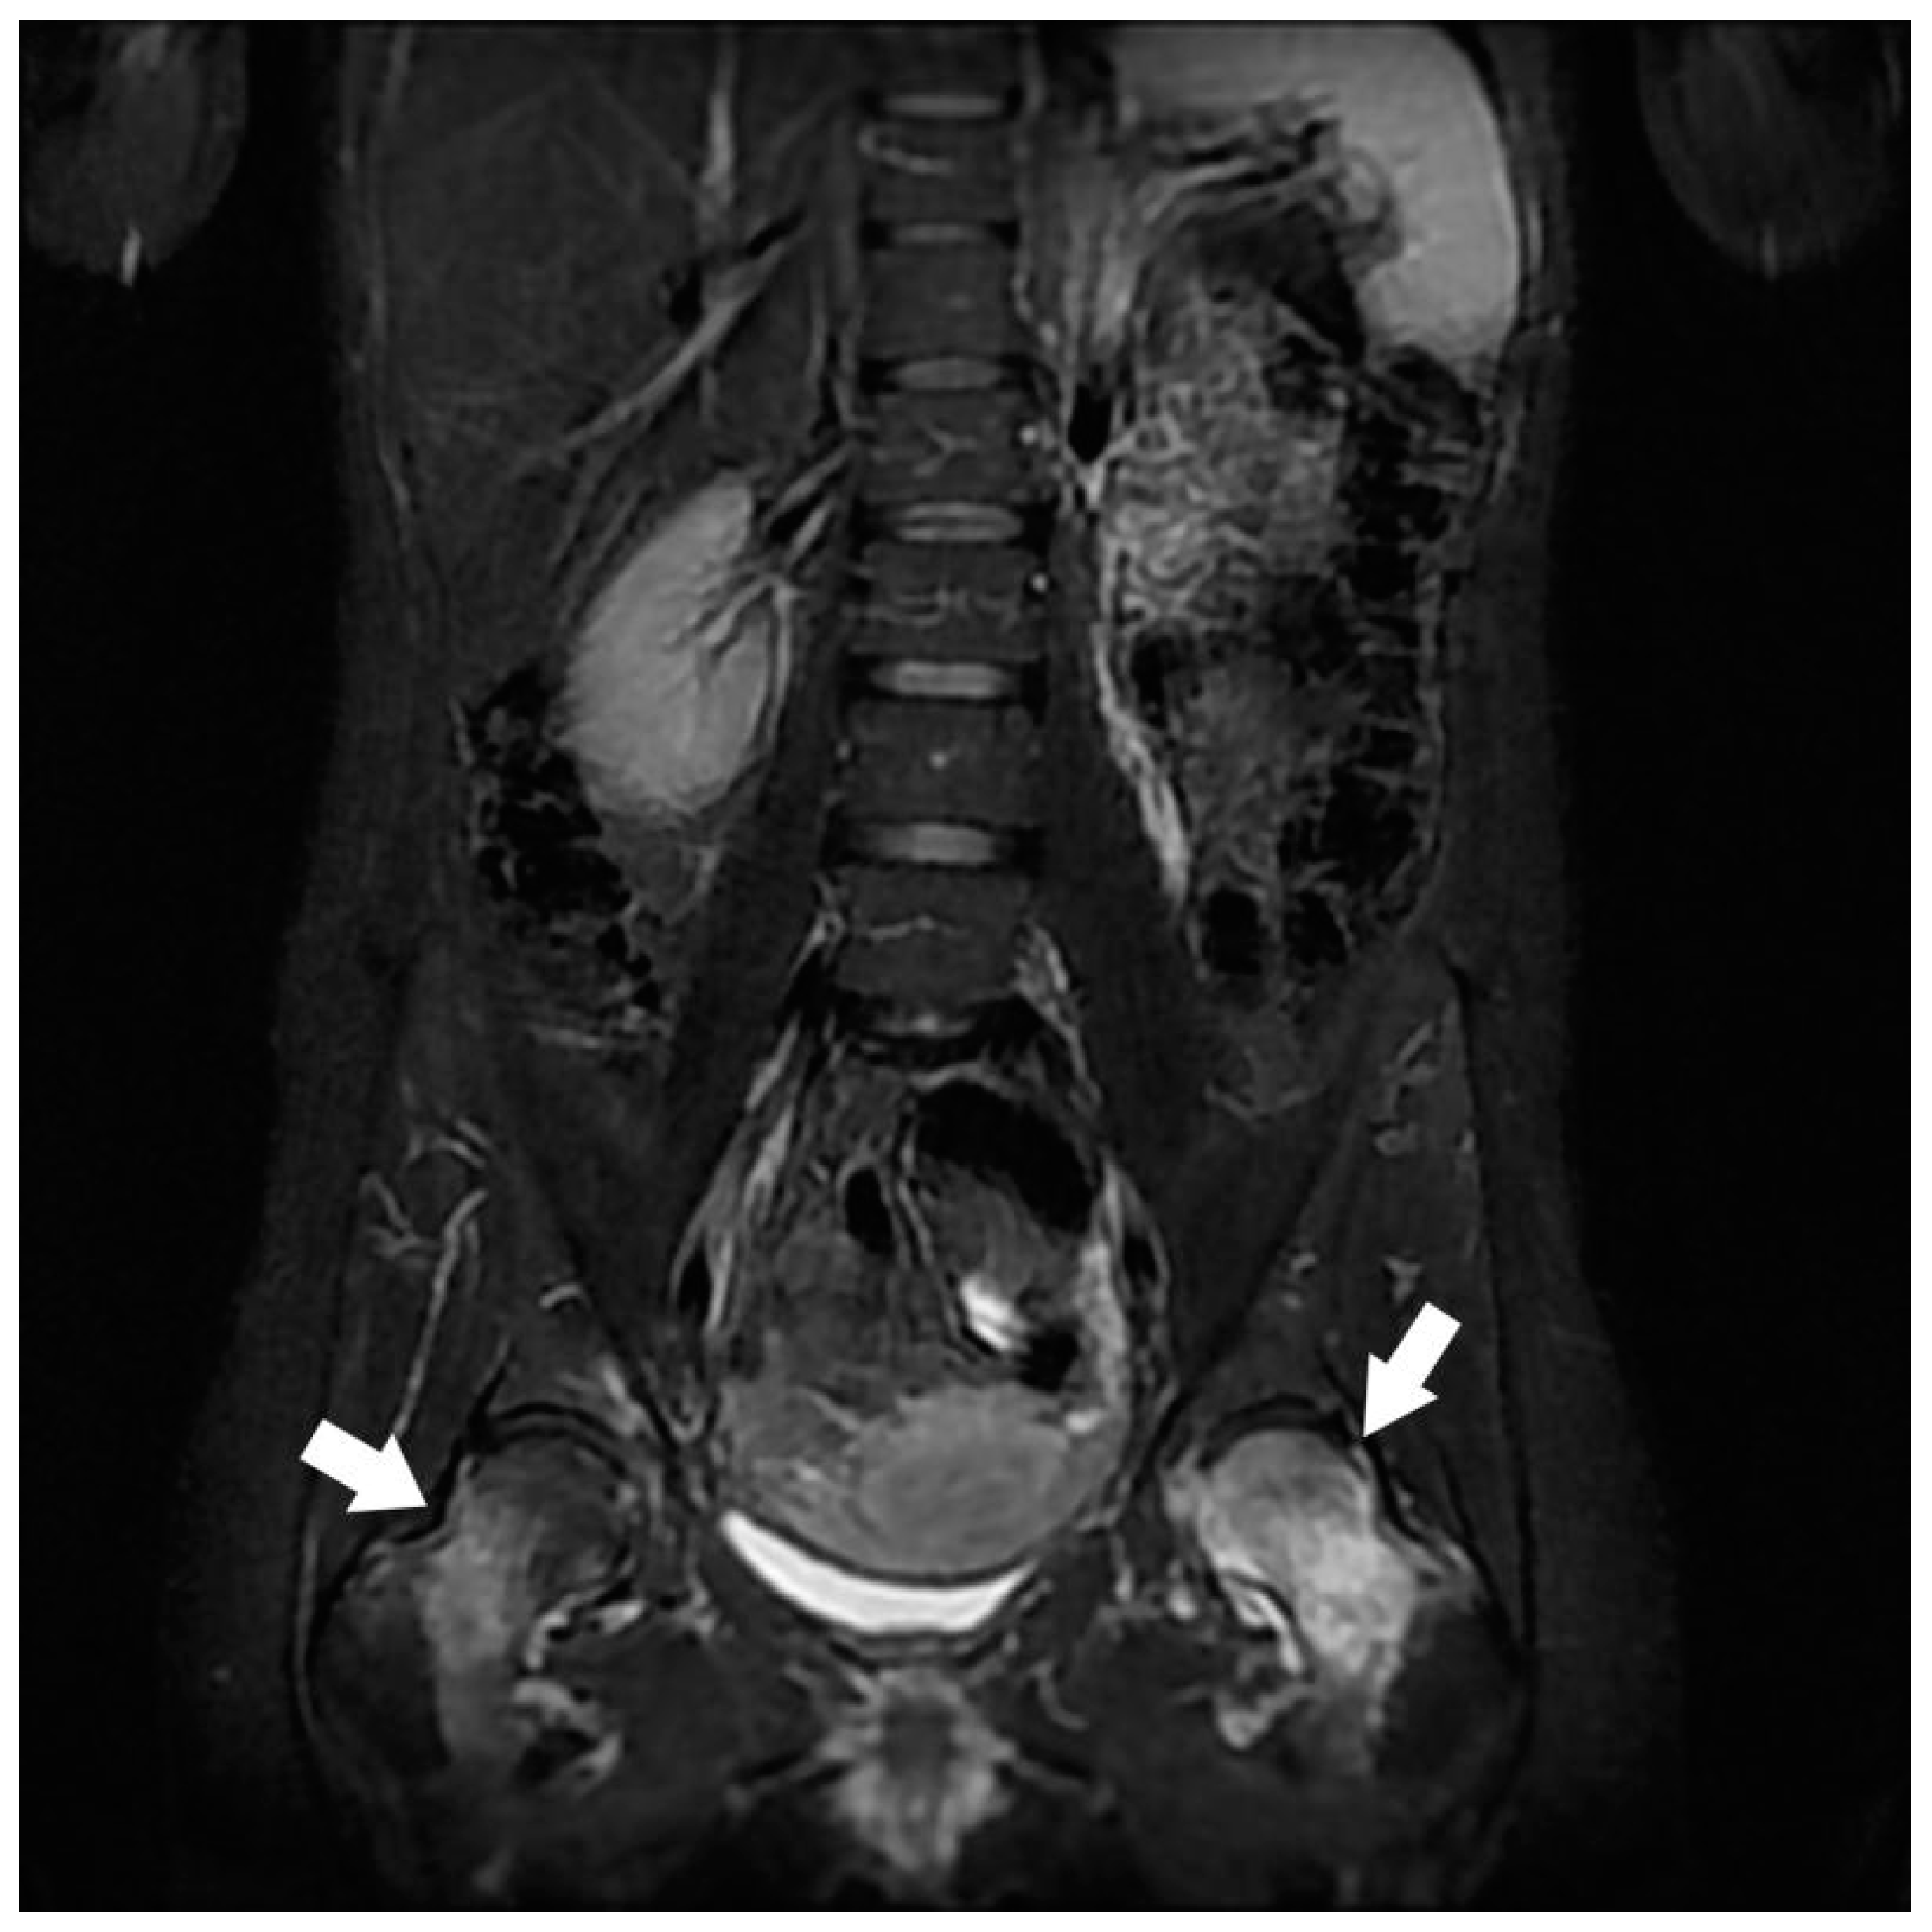

| Hip Joint | Congestive hip osteoarthritis | 17 |

| Stress femoral fracture | 4 | |

| Avascular femoral osteonecrosis | 1 | |

| Extensive acetabular edema | 1 | |

| Gluteal Muscles | Gluteal tendinobursitis | 21 |

| Sacroiliac Joint | Congestive degenerative arthropathy | 10 |

| Inflammatory sacroiliitis | 4 | |

| Sacral fracture | 1 | |